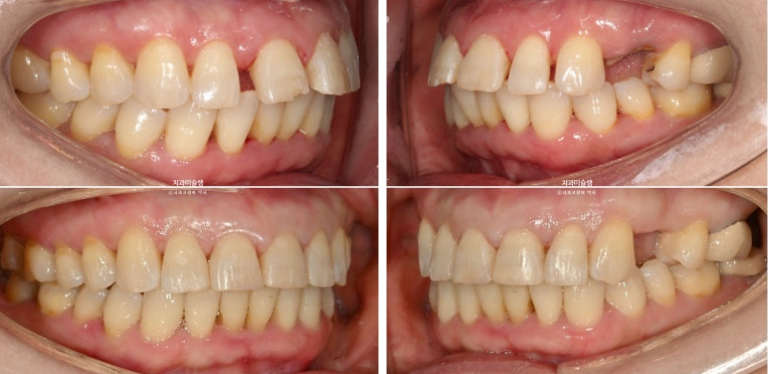

이제 전후 비교해보겠습니다.

24.07~26.01

앞니 각도의 개선이 눈에 띕니다.

아래 앞니는 치간삭제와 함입으로 위 앞니 사이사이 벌어진 공간을 이용하여 뻗친 각도와 골출을 개선하였으며

위 아래 앞니 각각 1.5-2mm 가량 뒤로 들어갔습니다.

일년 반에 걸친 치료기간동안 치근흡수는 없고 치근평행도는 좋습니다.

1년 반 치료기간동안 뻗쳐있던 위 아래 앞니 각도가 개선이 되니 입술도 좀 더 편하게 다물립니다.